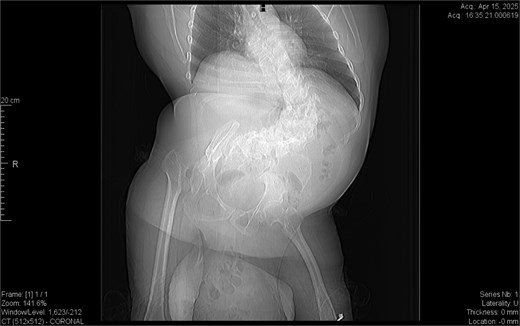

CT imaging (Figs 2–5) revealed a right inguinal hernia containing small bowel loops, ascending colon, the second and third portions of the duodenum, and the pancreatic head. The pancreatic head appeared rotated and displaced inferiorly into the hernia sac, without signs of acute pancreatitis.

Coronal CT view inguinal hernial sac with pancreatic head and D2 and D3 segment of duodenum.

Additionally, incidental findings (Fig. 2) included multiple calculi within the left hepatic duct. Though the patient was asymptomatic from a hepatobiliary standpoint, the presence of these stones raised concern for potential biliary stasis.